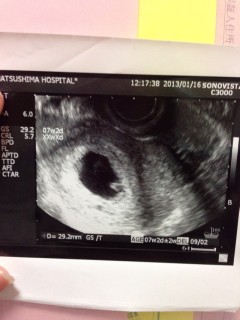

7w2d

やっと心拍が確認できました!

頭殿長13.9mm。